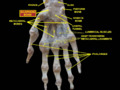

Scaphoid bone (left hand) 01 palmar view.png

Left hand anterior view (palmar view). Scaphoid bone shown in red.

The scaphoid bone is one of the carpal bones of the wrist. It is situated between the hand and forearm on the thumb side of the wrist (also called the lateral or radial side). It forms the radial border of the carpal tunnel. The scaphoid bone is the largest bone of the proximal row of wrist bones, its long axis being from above downward, lateralward, and forward. It is approximately the size and shape of a medium cashew.

The scaphoid is situated between the proximal and distal rows of carpal bones. It is located on the radial side of the wrist, and articulates with the radius, lunate, trapezoid, trapezium and capitate.[1]:176 Over 80% of the bone is covered in articular cartilage.[2]